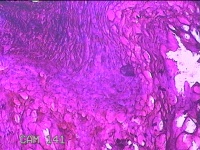

左侧膝关节皮下结节

性别

女

年龄

40岁

临床诊断

皮下结节

一般病史

发现左侧膝关节皮下结节1天。

标本名称

大体所见

灰白暗红色结节0.8x0.7x0.3cm一个,表面糜烂,切开结节呈实性,切面灰白粉红色,质软。